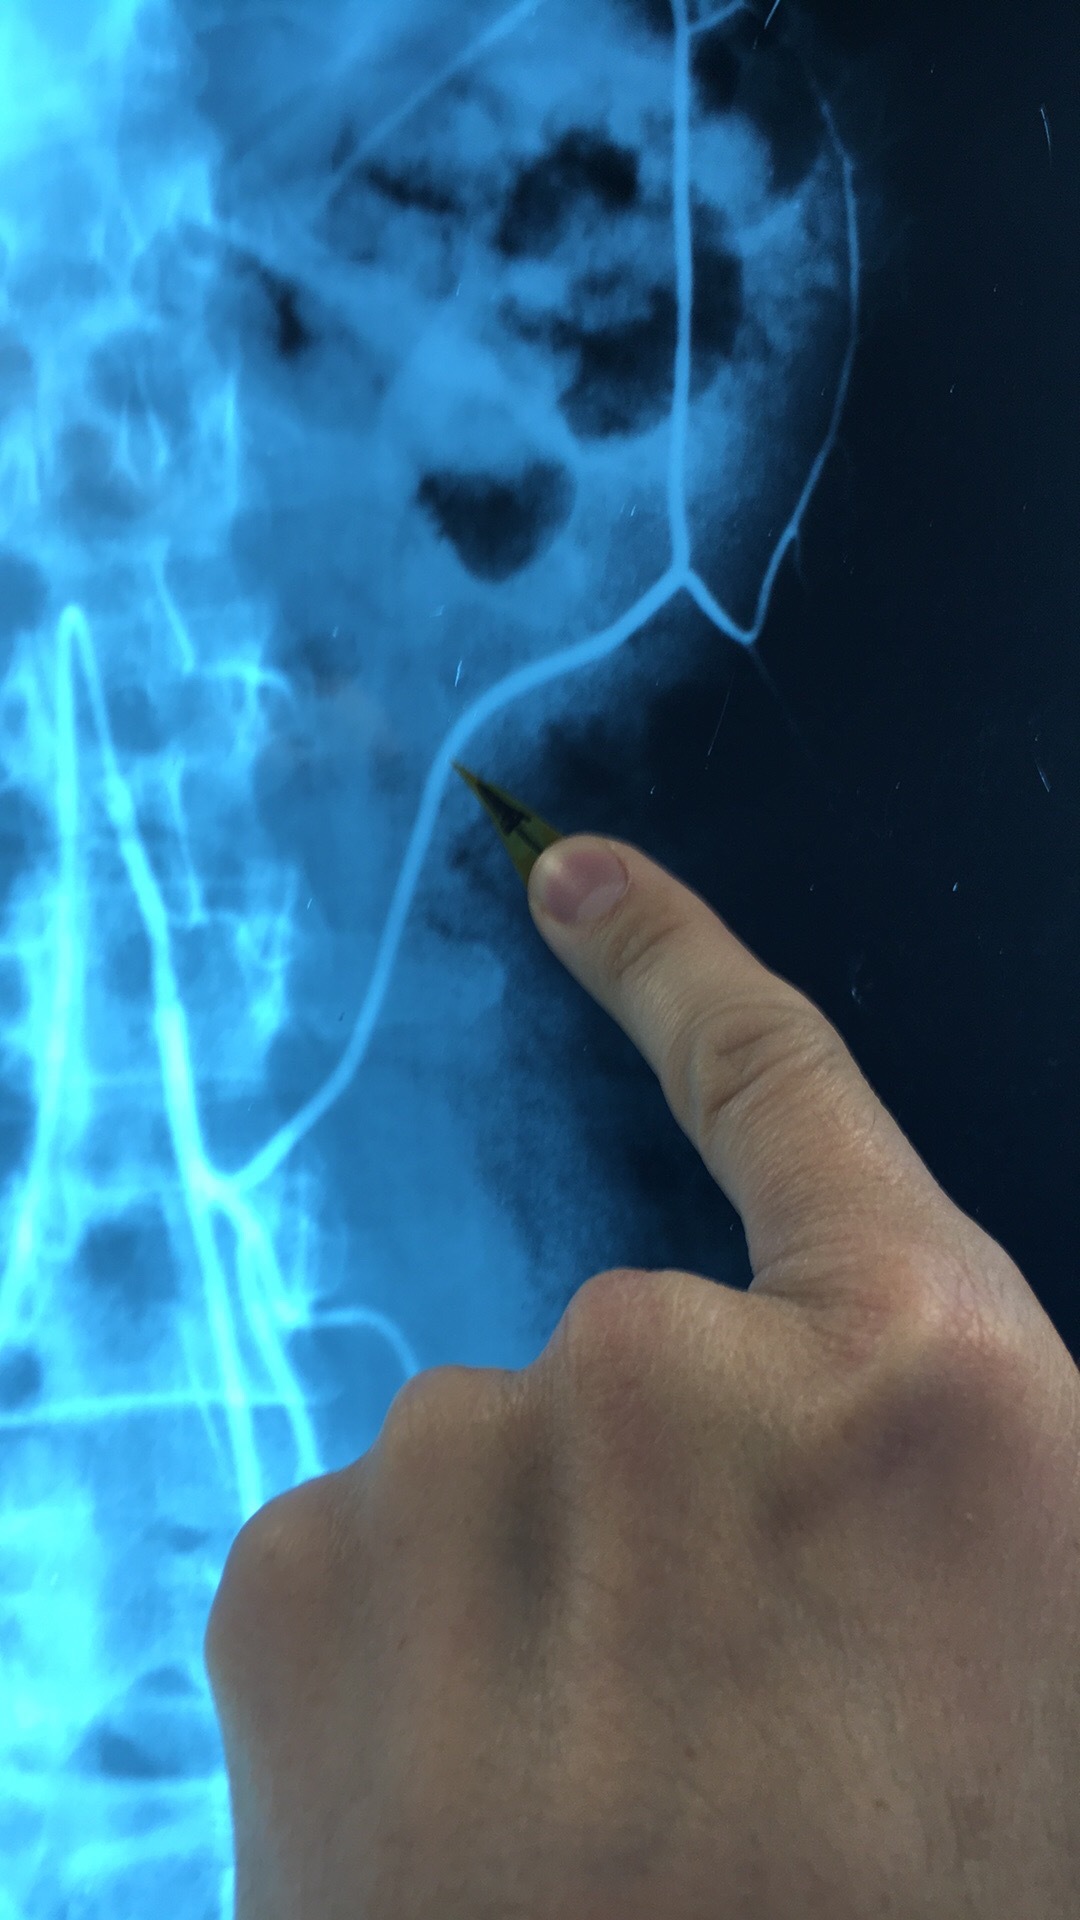

What artery? What comes off it?

Celiac Trunk. Left Gastric Art, Splenic Artery, Common Hepatic Artery